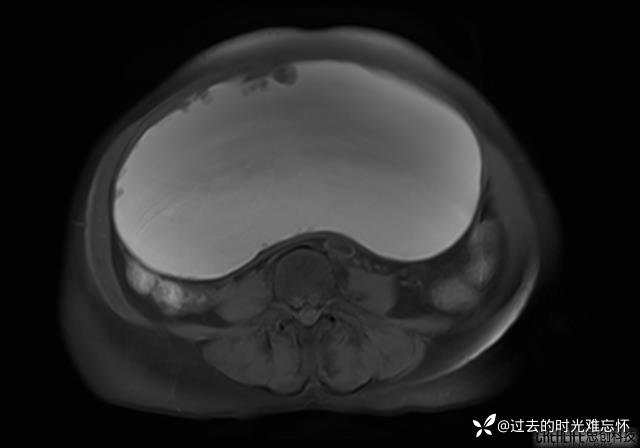

患者性别:女

患者年龄:65岁

主诉: 发现腹部隆起半年余。无其他明显不适。

浆液性囊腺瘤 (22)